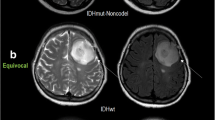

Tables 2 and 3 give the (semi-)quantitative measurements of aMRI for LGOs and HGOs. Relevant MRI images are depicted in Figs. 1 and 2. nADC values from DWI were significantly higher in LGOs than in HGOs (P < 0.001). ITSS levels of HGOs were substantially greater than that of LGOs with seven (46.7%) HGOs which exerted an agglomerated or nodular appearance of ITSSs (P = 0.006). Both nCBV and nCBF values in HGOs were significantly higher than the values of LGOs (P < 0.001 and P = 0.005).

A 50-year-old woman with molecularly defined HGO. On axial T2WI (a), the lesion shows heterogeneous signals with possible cystic or necrotic regions. Markedly nodular contrast enhancement is demonstrated on CE-T1WI (b). Corresponding ADC maps (c) exhibit a partially decreased ADC value (nADC = 0.85). rCBV maps (d) show significantly elevated perfusion with a nCBV value of 4.69. SWI reveals (e) a maximum degree of ITSSs. H&E staining (×400) photomicrograph (f) reveals relatively high cellularity and proliferative vessels